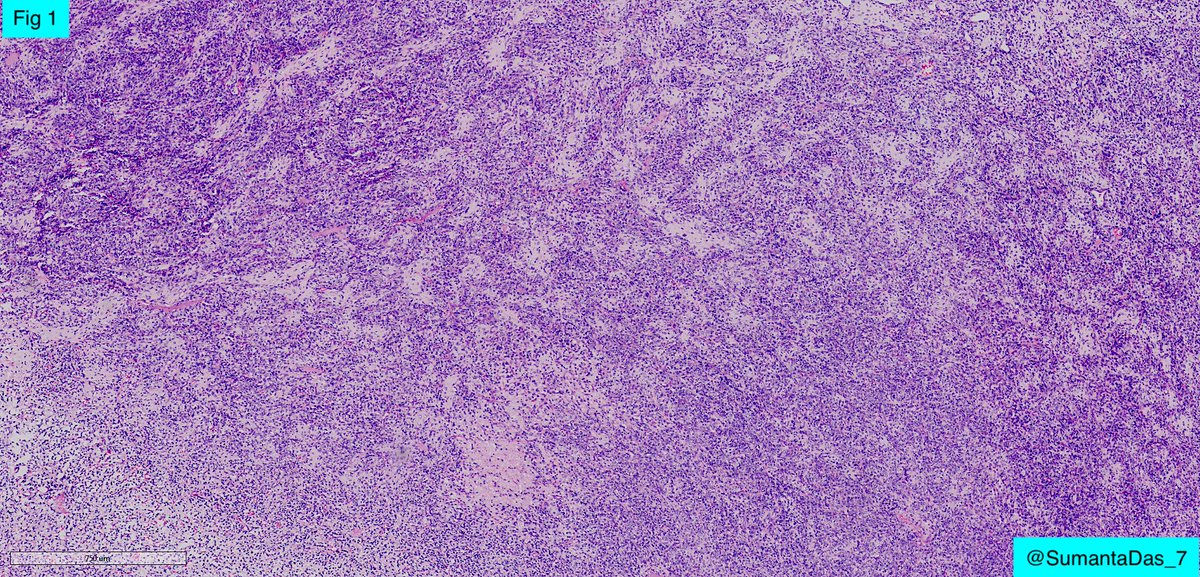

Adult Male. Dura based lesion. #PathX #PathTwitter #PathClassic #BSTPath #NeuroPath